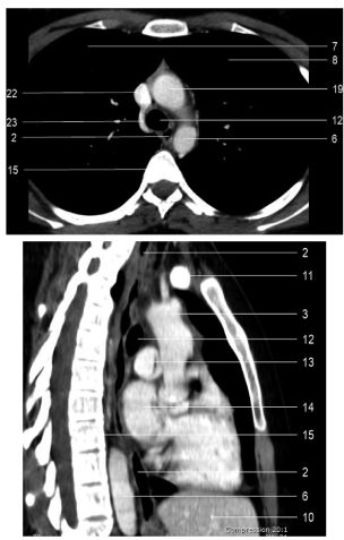

Fig. 2.7 Coupe tomodensitométrique axiale médiothoracique et reconstruction sagittale passant par l’œsophage.

2. Œsophage. 3. Aorte. 6. Aorte thoracique descendante. 7. Poumon droit. 8. Poumon gauche. 10. Foie. 11. Veine brachiocéphalique gauche. 12. Trachée. 13. Artère pulmonaire. 14. Atrium gauche. 15. Rachis dorsal. 19. Arc de l’aorte. 22. Veine cave supérieure. 23. Arc de la veine azygos.

Source : CERF, CNEBMN, 2022.